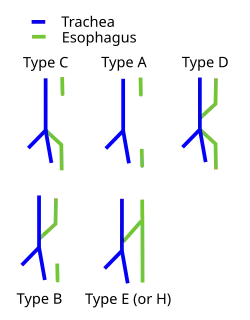

Fistulae between the trachea and esophagus in the newborn can be of diverse morphology and anatomical location.[6][7] However, various pediatric surgical publications have attempted a classification system based on the below specified types.

Not all types include both esophageal agenesis and tracheoesophageal fistula, but the most common types do.

| Gross | Vogt[8] | Description | EA? | TEF? |

|---|---|---|---|---|

| - | Type 1 | Esophageal agenesis. Very rare, and not included in the classification by Gross.[9] | Yes | No |

| Type A | Type 2 | Proximal and distal esophageal bud—a normal esophagus with a missing mid-segment. | Yes | No |

| Type B | Type 3A | Proximal esophageal termination on the lower trachea with distal esophageal bud. | Yes | Yes |

| Type C | Type 3B | Proximal esophageal atresia (esophagus continuous with the mouth ending in a blind loop superior to the sternal angle) with a distal esophagus arising from the lower trachea or carina. (Most common, up to 90% of cases.) | Yes | Yes |

| Type D | Type 3C | Proximal esophageal termination on the lower trachea or carina with distal esophagus arising from the carina. | Yes | Yes |

| Type E (or H-Type) | - | A variant of type D: if the two segments of esophagus communicate, this is sometimes termed an H-type fistula due to its resemblance to the letter H. TEF without EA. | No | Yes |

The letter codes are usually associated with the system used by Gross,[10] while number codes are usually associated with Vogt.[11]

An additional type, "blind upper segment only" has been described,[12] but this type is not usually included in most classifications. (For the purposes of this discussion, proximal esophagus indicates normal esophageal tissue arising normally from the pharynx, and distal esophagus indicates normal esophageal tissue emptying into the proximal stomach.)